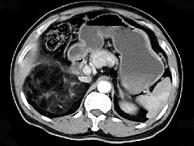

问题 男,59岁,右侧腰背酸痛,CT检查如图所示,应诊断为()

选项 A.右肾上腺腺瘤 B.右肾上腺转移瘤 C.右肾上腺髓样脂肪瘤 D.右腹膜后脂肪瘤 E.右肾血管平滑肌脂肪瘤

答案 C